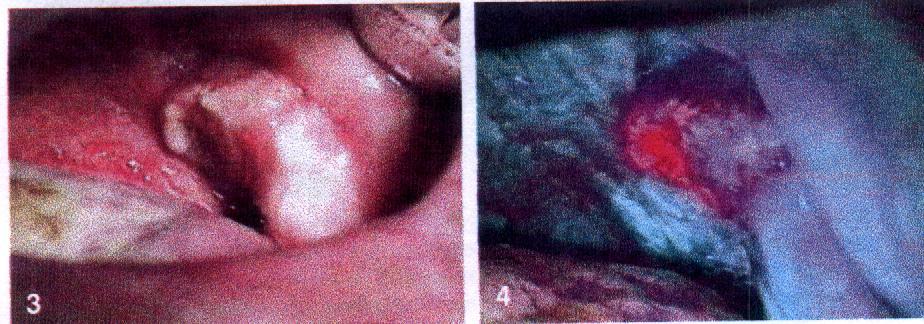

Selbst kleine Geschwü-re und Vorstadien, sogenannte in-situ-Tumore, offenbaren sich dem Auge der Mediziner. Prof. Witold Zenk und sein Team wenden deshalb die neue Fluoreszenz-Methode nicht nur in der Diagnostik an, sondern auch, um vor der Operation den Tumor genau zu markieren. Zenks Mitarbeiter Dr. Peter Schleier: "Wir sehen dann deutlich, wie weit der Krebs das gesunde Gewebe infiltriert hat."

Gewundert haben sich die Jenaer Forscher anfangs über häufige Fehldiagnosen bei Patienten mit schlechter Mundhygiene. Inzwischen haben sie dank der Hilfe des Jenaer Mikrobiologen Prof. Dr. Wolfgang Pfister herausgefunden, dass dafür Mundbakterien wie Staphylococcus aureus oder Prevotella oralis verantwortlich sind. Diese Erreger siedeln nicht nur an Zahnhälsen, sondern auch im abgestorbenen Zentrum eines Krebsgeschwürs. Die einfache Lösung des Problems: Bevor der Patient zur ALA-Spülung greifen darf, muss er den Mund mit einem - in der Zahnheilkunde üblichen - desinfizierenden Mittel reinigen. Das Ergebnis: Die Fehlerquote sank rapide, und Tumore werden nun noch viel trennschärfer sichtbar.